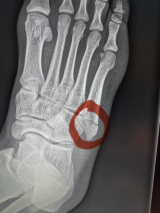

- 骨折した箇所を示すレントゲン写真@ManelKapeより

I suffered a foot fracture during training and, after medical evaluation, I was instructed to have surgery and focus 100% on recovery.